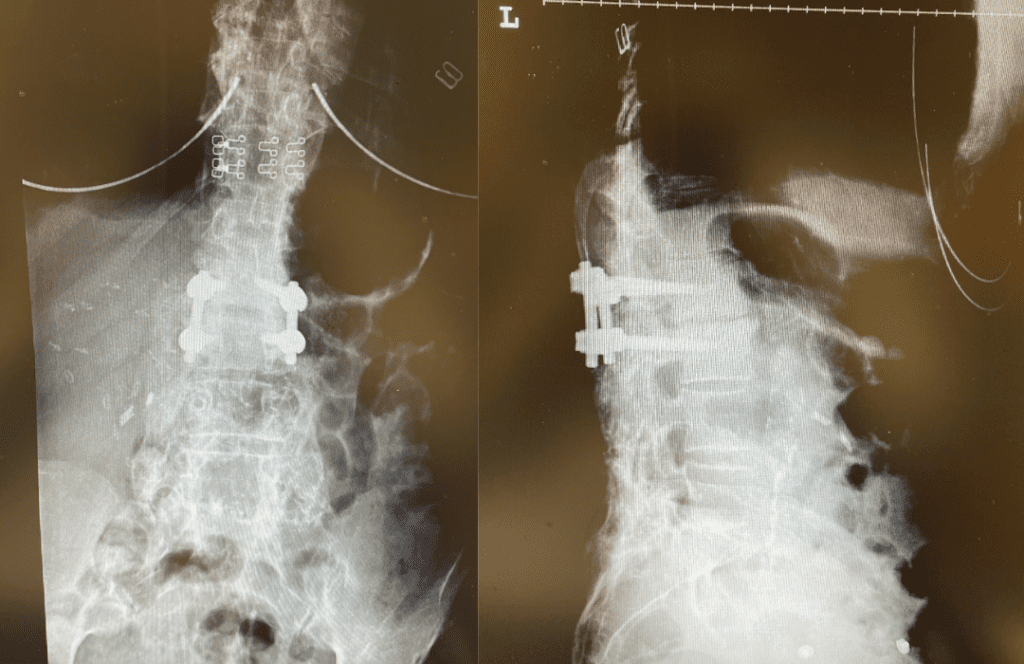

This 62-year-old female presents with chronic intractable low back pain with radiation down the front of her thighs. The patient had had two prior fusion surgeries: She initially had an L4-S1 fusion twelve years prior and a subsequent revision extension of her fusion at L3-4 that she had three years prior. She had a long-term history of smoking. She had mild hip flexor weakness, right greater than left. Imaging studies revealed next segment degeneration and stenosis at L2-3 (Figs. 1a and 1b and 2).

Figure 2. Axial T2 MRI of the lumbar spine demonstrating L2-3 stenosis due to significant facet arthropathy.